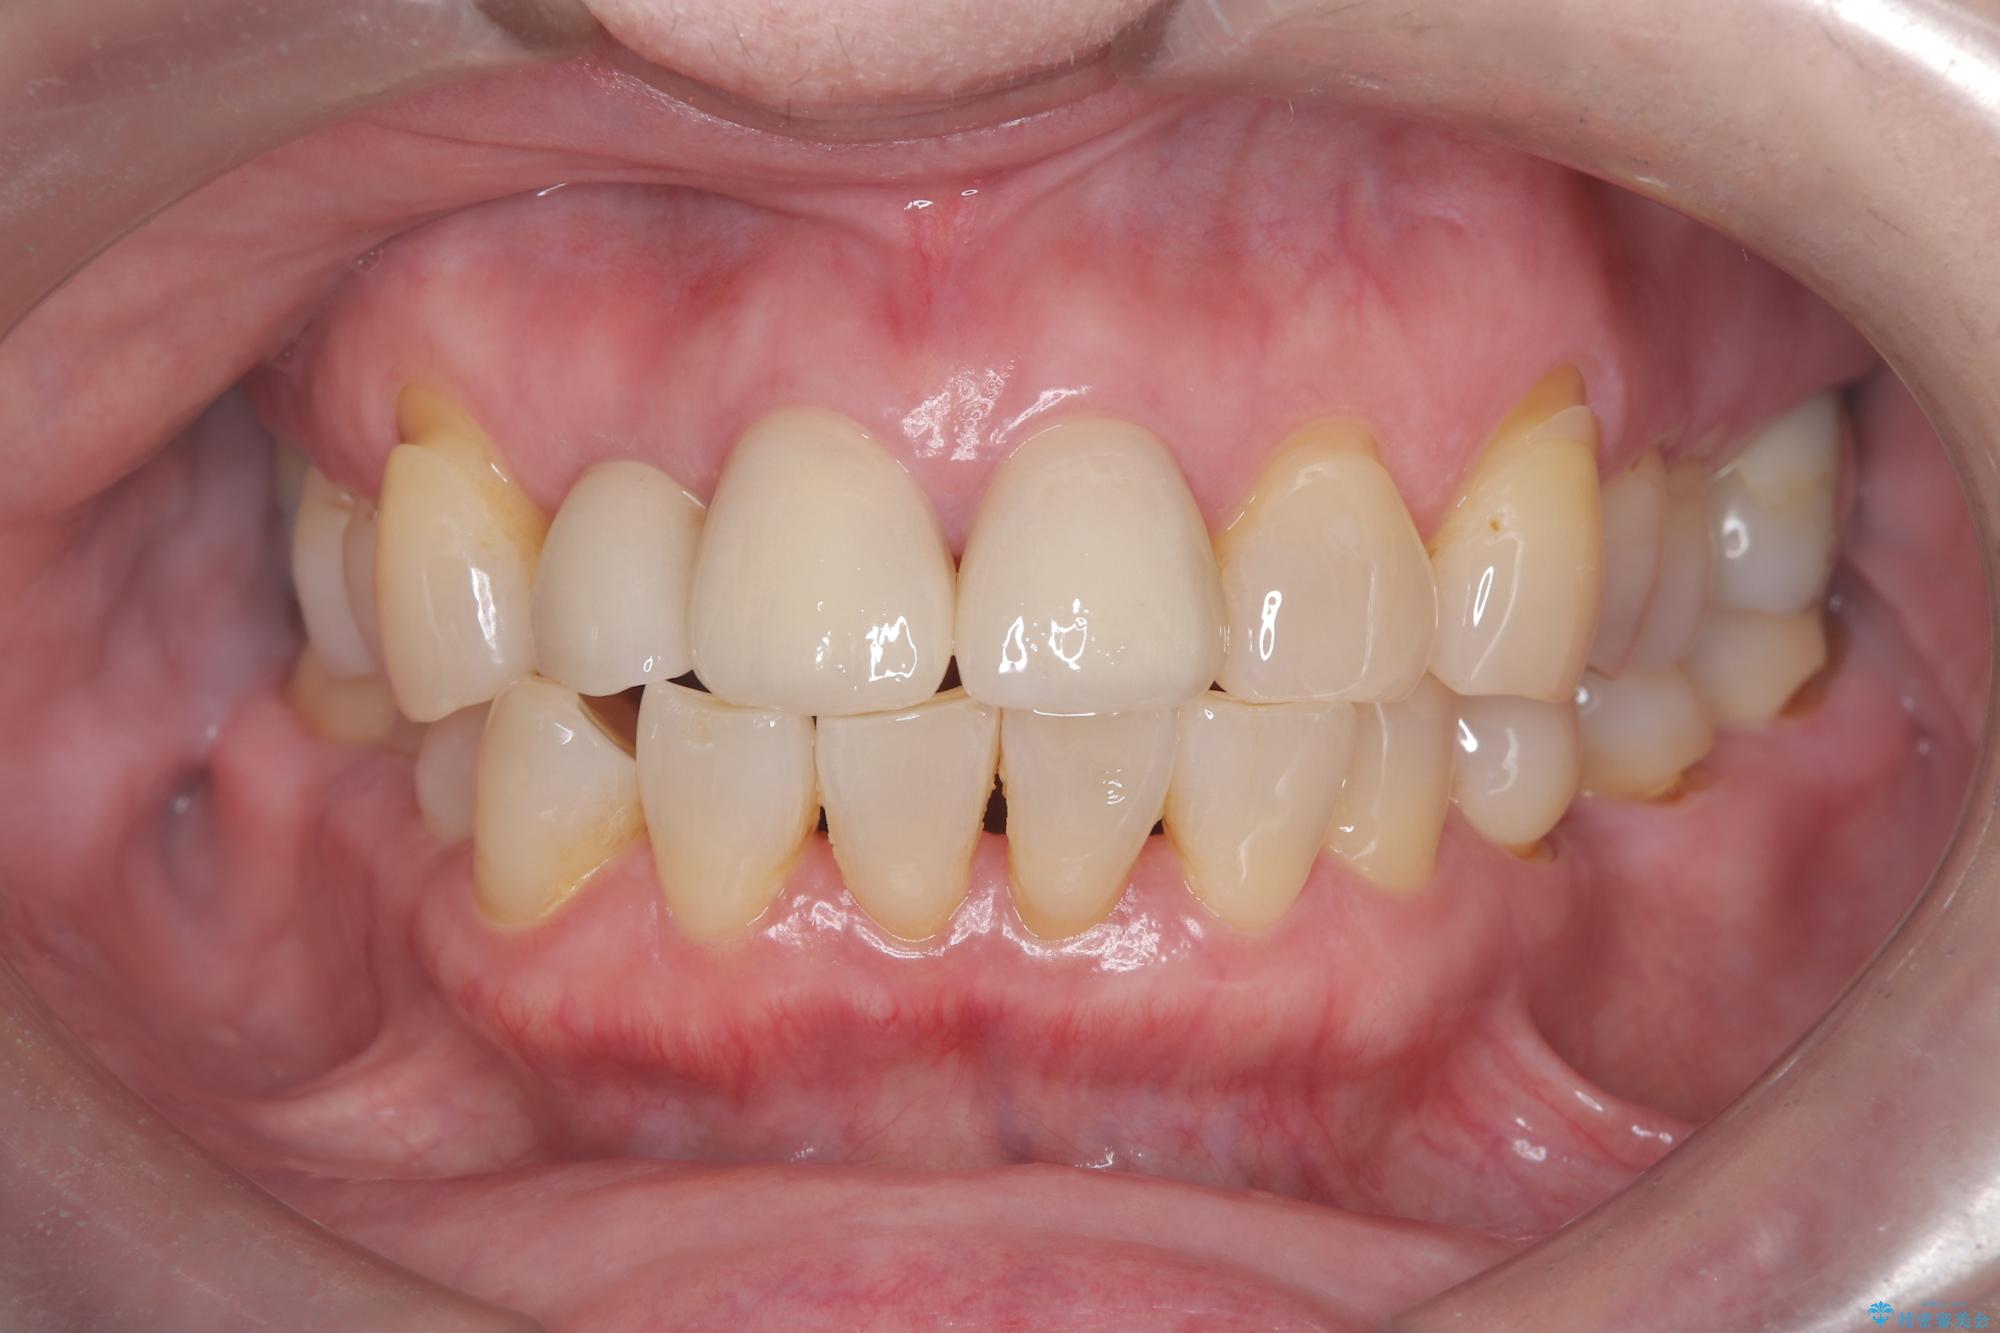

そのため今回は、右上2番を抜歯し、右上1番および左上1番をオールセラミッククラウンで審美的に修復しました。

矯正によって歯並びや咬み合わせを整えた後、必要に応じて歯の形や色を整えるためにホワイトニングやセラミック治療を行うことで、より自然で美しい仕上がりが期待できます。

治療期間も短く、抜歯からわずか3か月でオールセラミッククラウンを装着することができます。

また、オペ当日には仮歯まで装着するため、見た目を気にせず普段通りの生活を送ることができます。